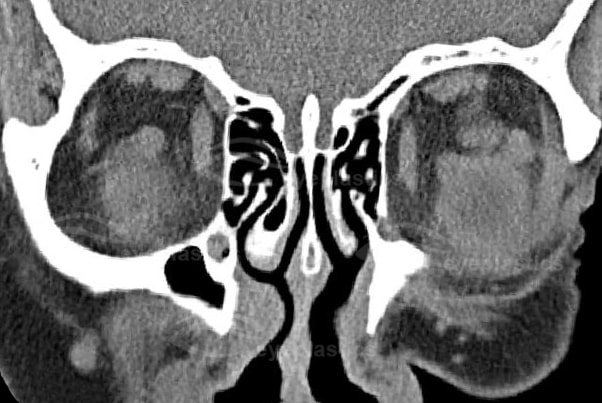

- CT scan detects an oval or round, homogenous mass with sharp margins, but falls short of a definitive diagnosis.

Imaging of Cavernous Hemangioma

- CT: smooth discrete lesion, fills with dye after 20 min; coronal cuts important to know tumor position relative to optic nerve. for sugical plan

- MRI: hypointense to fat on T1, hyperintense to fat on T2

- U/S: high reflectivity (A-scan high amplitude internal echoes)